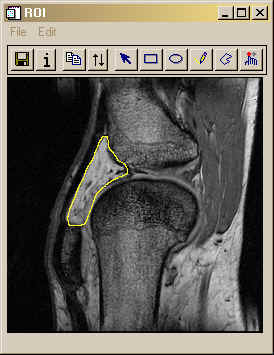

Alternatively, you could mask all of the rest of the image out, and just keep the ROI:

IDL> roiImage = image * (mask GT 0) IDL> TV, roiImage

Here is the result in the figure below.